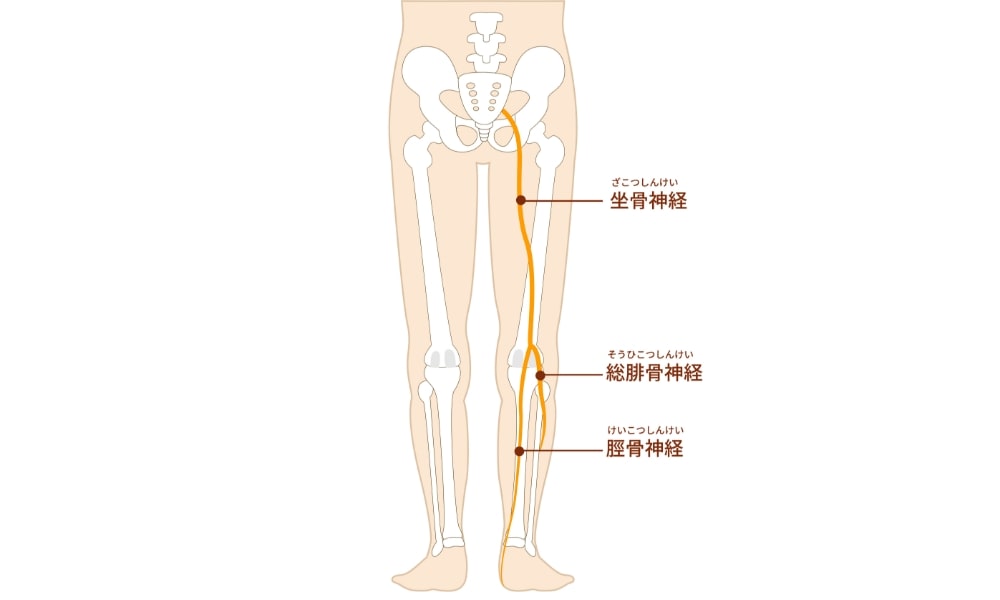

椎間板の内部のゼリー状の組織が飛び出て神経を圧迫することで、腰だけでなく下肢の痛み・しびれ(坐骨神経痛)を伴うことがあります。 - 脊柱管狭窄症

椎間板ヘルニア・坐骨神経痛を伴うもの

特徴

- 椎間板が突出して神経を刺激・圧迫

- 腰痛・下肢への放散痛・しびれを伴う

主な症状

- 腰痛だけでなく、足の痛み・しびれ・感覚異常

- 長時間座ると悪化、寝返りや立ち上がりで痛みが強くなる

- 下肢筋力低下や反射異常を伴う場合あり